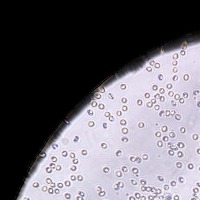

RBC Platelet v1 Computer Vision Project

Medical Diagnostic Tools: "RBC Platelet v1" can be integrated into diagnostic software systems to help physicians automatically detect and classify blood cells, aiding in faster disease diagnosis such as anemia, leukemia, or thrombocytopenia.

Biological Research: Researchers studying blood cells and diseases could use this model to automate cell identification and classification in their lab results, making for a more efficient research process.

Blood Donation Centers/Banks: The model can be used to analyze blood donations for cell counts automatically, creating a more efficient processing and safety screening.

Pharmaceutical Development: Companies can use this model in drug development processes, especially when testing the effects of new medication on blood cells, as it allows for the automatic identification and tracking of cell changes.